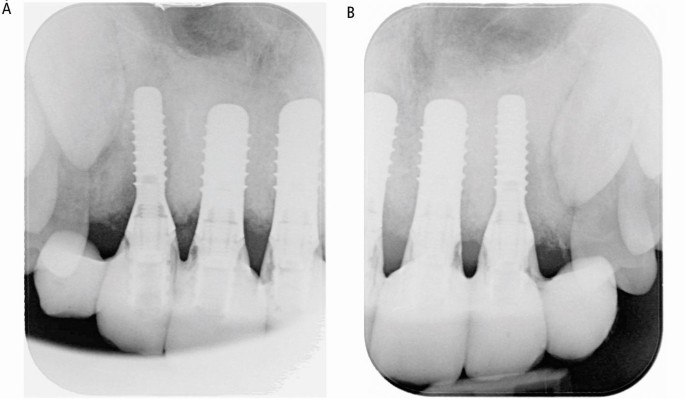

(A, B) Case 1: peri-apical radiographs showing the implants placed in the anterior maxilla

Six months later, restoratively driven implant placement with four implants in the maxilla and two in the mandible at an insertion torque of 35 Ncm was undertaken (Fig. 6). Despite the fibrous nature of the bone, high primary stability was achieved and healing one week later was uneventful. A provisional bridge was fitted five months after the surgery in the maxilla and crowns fitted in the mandible (Fig. 7). The radiographs taken post-fit (Fig. 8) showed the ground-glass bone appearance. The radiolucency seen on the distal of the lateral incisor implants could be the healing response of the CFD as clinically there was no pocketing, bleeding or inflammation noted around the implants. The patient was delighted with the outcome.